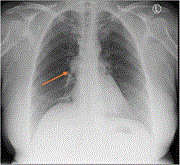

Right upper lobe pulmonary sequestration masquerading clinically and radiologically as malignancy: a case report

Ankit Gupta and others

Journal of Surgical Case Reports, Volume 2023, Issue 1, January 2023, rjad022, https://doi.org/10.1093/jscr/rjad022